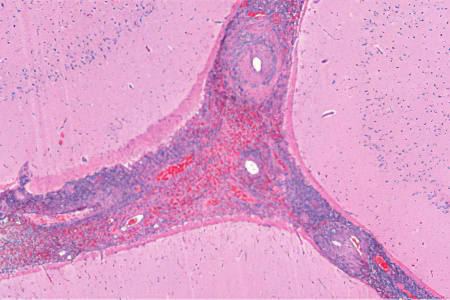

- Биопсия почек и кожи.